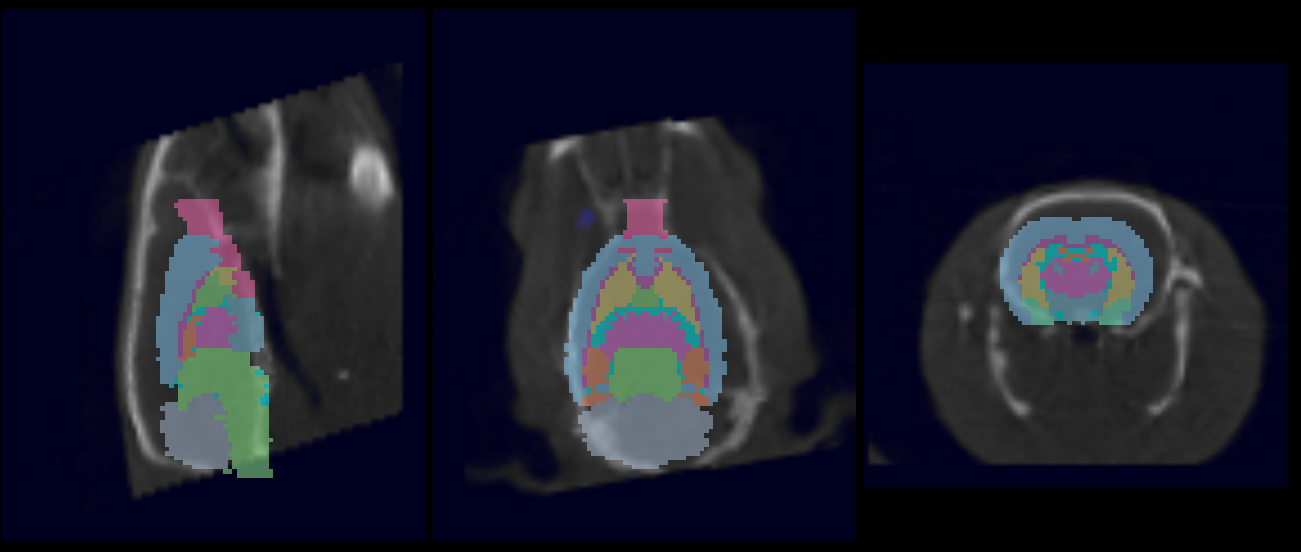

The 3D Brain Atlas Analysis Tool is designed for automatic segmentation of brain image data. Automated fusion routines register an application-specific brain atlas to pre-clinical image data (or vice versa) and advanced statistical analysis methods are employed to provide rapid and thorough region-specific volume and uptake quantification.

Use the 3D Brain Atlas Tool to perform brain region analysis. The tool can handle CT or MR data as the input and MR, PET, or SPECT for the input functional data.

| atlasFinal.rhma | The output brain ROI |

- When the tool finishes, results will load automatically (including the CSV file) and VQ will finish in the 3D ROI tool.